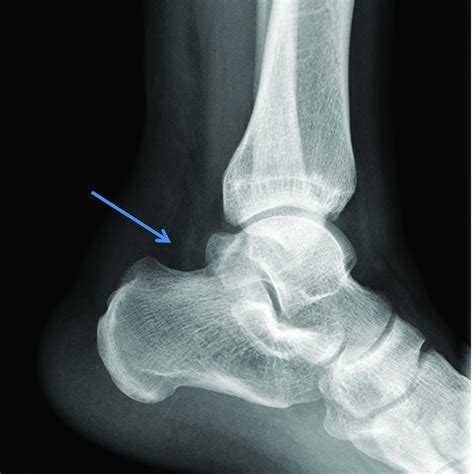

Diagnosis of Achilles Tendon Rupture

Diagnosing an Achilles tendon rupture typically involves a physical examination and imaging tests. During the physical examination, the healthcare provider will assess the range of motion, strength, and flexibility of the affected foot and ankle. They may also perform the Thompson test, which involves squeezing the calf muscle to see if the foot moves. If the foot does not move, it may indicate a ruptured Achilles tendon.

Imaging tests, such as ultrasound or magnetic resonance imaging (MRI), can provide a more detailed view of the tendon and confirm the diagnosis. These tests can also help determine the extent of the injury and guide treatment decisions.